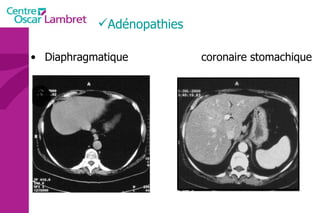

Adénopathies Diaphragmatique coronaire stomachique

Adénopathies